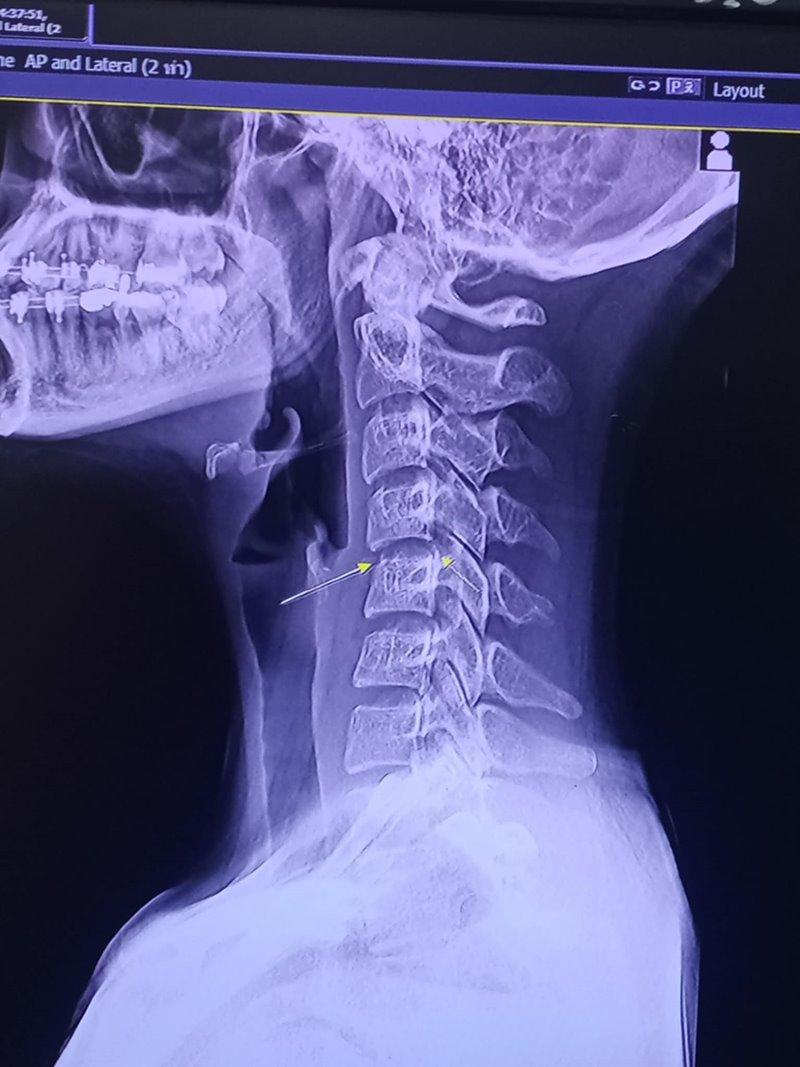

เป็นข่าวเศร้าสลดกับการเสียชีวิตของนักร้องสาว ผิง ชญาดา ซึ่งได้จากไปเมื่อเวลา 06.08 น. วันนี้ (8 ธันวาคม 2567) โดยพบว่าก่อนหน้านี้ ผิง ชญาดา ได้โพสต์เล่าอาการผิดปกติกับความทรมานที่เกิดขึ้น หลังไปนวดบิดคอ จนทำให้ร่างกายอ่อนแรง จนสุดท้ายก็ช่วยเหลือตัวเองไม่ได้ ต้องอยู่ในสภาพติดเตียง รวมถึงเพจดังต่าง ๆ ได้ออกมาโพสต์เตือนถึงอันตรายเกี่ยวกับการนวด โดยเฉพาะบริเวณคอ